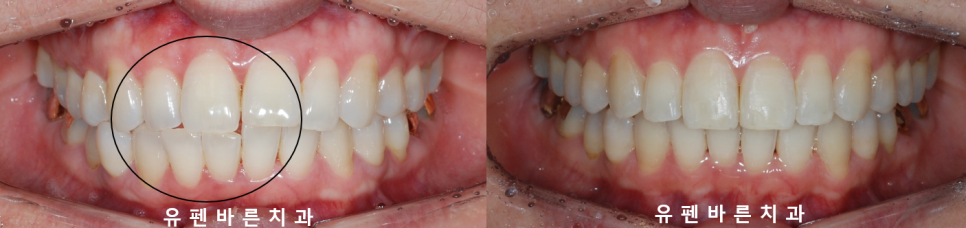

28개의 인비절라인라이트 옵션으로

유지장치까지 새롭게 깔끔히 부착되고

마무리된 모습인데요

결과적으로

앞니끼리 닿지 않아

앞니에 외상을 없애주고

양쪽 어금니가 맞물리게 되면서

식사도 잘 하실 수 있게 되어

앞니끼리 맞물려

짧아져 있던 뿌리가

안정되고

윗니가 아랫니를 약간 덮으면서

바르게 정상교합이 된 모습을

보실수 있는데요.